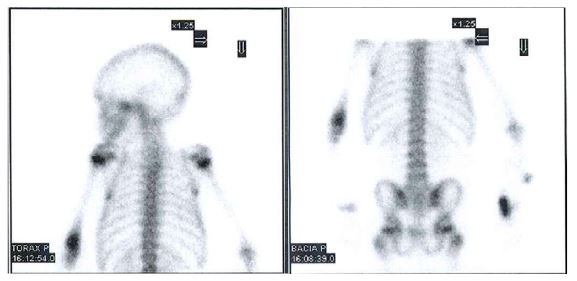

Due to persistence of complaints, a osteoarticular scintigraphy with Tc99m was performed on day 2 of hospitalization (Figure 1), which showed diffuse uptake of the radiopharmaceutical in the right tibiotarsal joint and in the bones of the right foot. At that time, fever persisted and there was a pattern of migratory pain in the lower limbs that woke the girl from sleep and led to a total refusal to walk.

Bone involvement in ALL can be translated radiologically into osteolytic lesions, metaphyseal bands, decreased bone density, osteosclerosis, pathologic fractures, and periosteal reactions.11,16 These and other changes may occur in 41-75% of children with ALL.10,12,13) Brix et al. reported changes in 61% of children who underwent osteoarticular scintigraphy, although it has limited diagnostic value in these situations.14 The alterations on scintigraphy were also confounding factors in both cases presented.